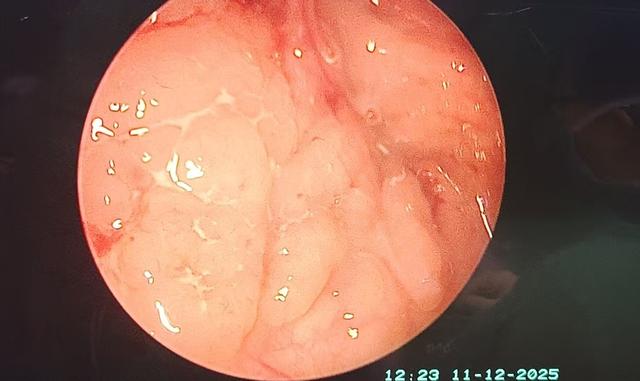

术前:腺样体肥大完全堵塞双侧后鼻孔,挤压双侧咽鼓管圆枕,堵塞咽鼓管